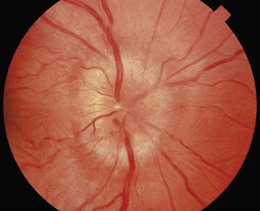

Fig. 12.22 Swollen optic disc.

Papilloedema is suggested if visual acuity is unaffected, colour vision is normal and there is an enlarged blind spot.

Optic disc: With a swollen and white optic nerve head (anterior ischaemic optic neuropathy), consider giant cell arteritis and polyarteritis nodosa and check markers of inflammation (raised erythrocyte sedimentation rate, C-reactive protein or platelet count) (Fig. 12.31C). Pseudophakic patients with artificial intraocular lenses following cataract extraction often have falsely pale discs. Increased cup-to-disc ratio (cupped disc) is seen with chronic open-angle glaucoma (a group of diseases of the optic nerve involving loss of retinal ganglion cells, associated with raised intraocular pressure and visual field loss). Typically, the vertical margins are affected first.

The optic disc is a common site for new vessel formation. In the presence of an enlarged blind spot, blurring of the optic disc indicates distension of the optic nerve sheath. Reduced colour vision and a relative afferent pupillary response suggest an intrinsic optic nerve lesion.